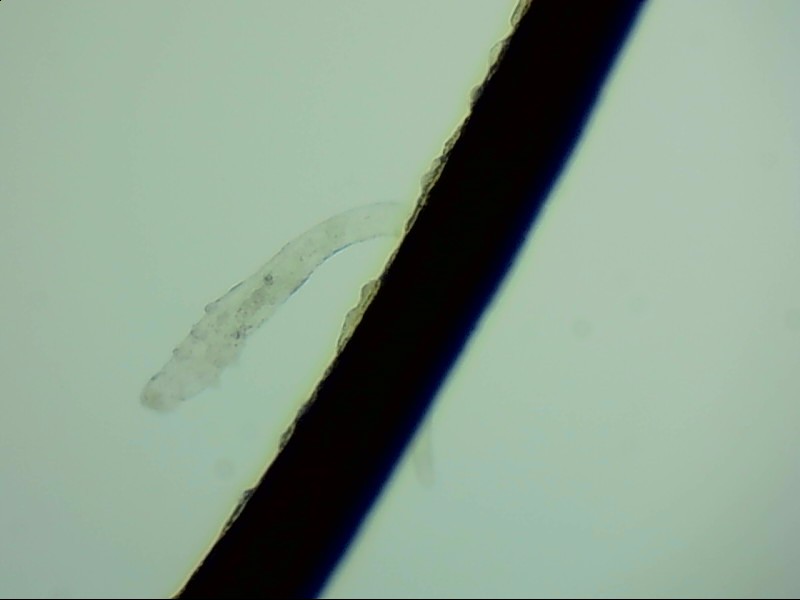

小張是一位程序員,長時(shí)間對著電腦,感覺眼干、有異物感在所難免。最近他除了眼干、難受,還發(fā)現(xiàn)眼睛發(fā)癢,掉落的睫毛上還會(huì)帶著絲狀的分泌物。剛發(fā)現(xiàn)時(shí)小張并沒有放在心上,但當(dāng)他在屏幕上看到睫毛上的螨蟲時(shí),他的心里一陣后怕,“原來我的睫毛上長著這么可怕的東西。”

螨蟲怎么會(huì)爬到睫毛里?廈門眼科中心蠕形螨性瞼緣炎門診張麗穎博士后介紹,人體螨蟲主要有兩種,一種是皮脂螨,主要寄生于皮脂腺和瞼板腺內(nèi);另一種是蠕形螨,“住”在睫毛毛囊里,晚上從毛囊里爬出來,白天躲在毛囊里產(chǎn)卵。

據(jù)介紹,這種疾病確診主要通過觀察睫毛里的螨蟲數(shù)量聯(lián)合瞼緣及眼表情況共同診斷。一般而言,如果12根睫毛里,有2條或是超過2條的螨蟲就可以被確診。如果檢查確實(shí)發(fā)現(xiàn)較多的蠕形螨感染,建議加上抗螨治療。張麗穎說,發(fā)現(xiàn)眼睛干澀、發(fā)癢,不要自行用藥,建議到醫(yī)院就診。如果長期反復(fù)多發(fā)霰粒腫,要考慮是否存在蠕形螨感染。